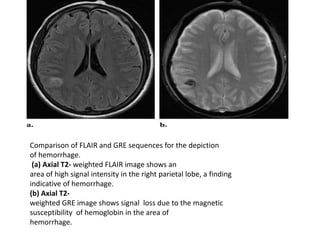

Comparison of FLAIR and GRE sequences for the depiction

of hemorrhage.

(a) Axial T2- weighted FLAIR image shows an

area of high signal intensity in the right parietal lobe, a finding

indicative of hemorrhage.

(b) Axial T2-

weighted GRE image shows signal loss due to the magnetic

susceptibility of hemoglobin in the area of

hemorrhage.